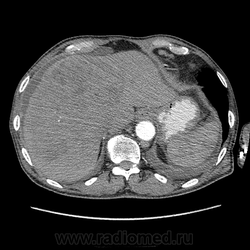

Печень. Процесс в средостении, бр.пол., забр.пр-ве. МСКТ.

Здравствуйте, коллеги! Мужчина около 70 лет. Жалобы: слабость, утомляемость около 3х месяцев, чувство тяжести на желудке после еды. Анамнез: онко не было. С вышеописанными жалобами обратился ко врачу, сделали ФГЭДС - признаки гастродуоденита, по биопсии - N. В течение 2х последних недель существенно похудел и начал желтеть. Выполнена МСКТ

А как насчет холангиокарциномы с тромбозом воротной вены и мтс в средостение, лимфоузлы брюшной полости и забрюшинного пр-ва?

Я - за.

Внимательно пересмотрел, признаков характерных для ГЦР не нашел (кроме тромбоза). Согласен с холангиокарциномой, ещё бы отсроченную фазу, для печени минут через 12-15 .

Для холангиокарциномы характерно гиперденсивность, в отсроченную фазу, за счет аффинитета к контрастному веществу.

Андрей Юрьевич, 5 минут маловато IMHO. Обычно делаю 10 мин на предмет соединительной ткани (до 15 мин будет не хуже)... А Вы?

Ну я уж, собственно, ответил. Холангиокарционома накапливает контраст, альвеококк - нет. И потом, холангиокарцинома, как правило, вызывает обструкцию желчных протоков, так что проксимальнее обструкции мы увидим их расширение - очень яркий признак на КТ.